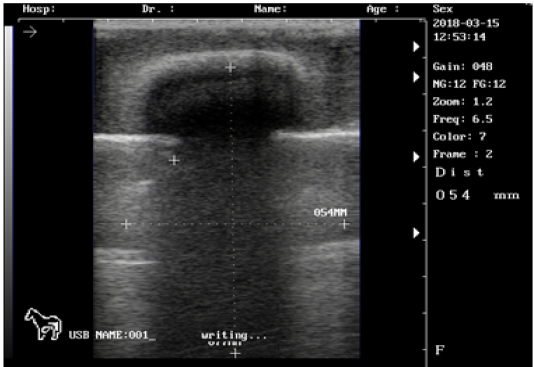

Ultrasound images of the testis of 6 months lamb showing: moderate echogenicity of the testicular parenchyma; mediastinum testicular moderately echogenic